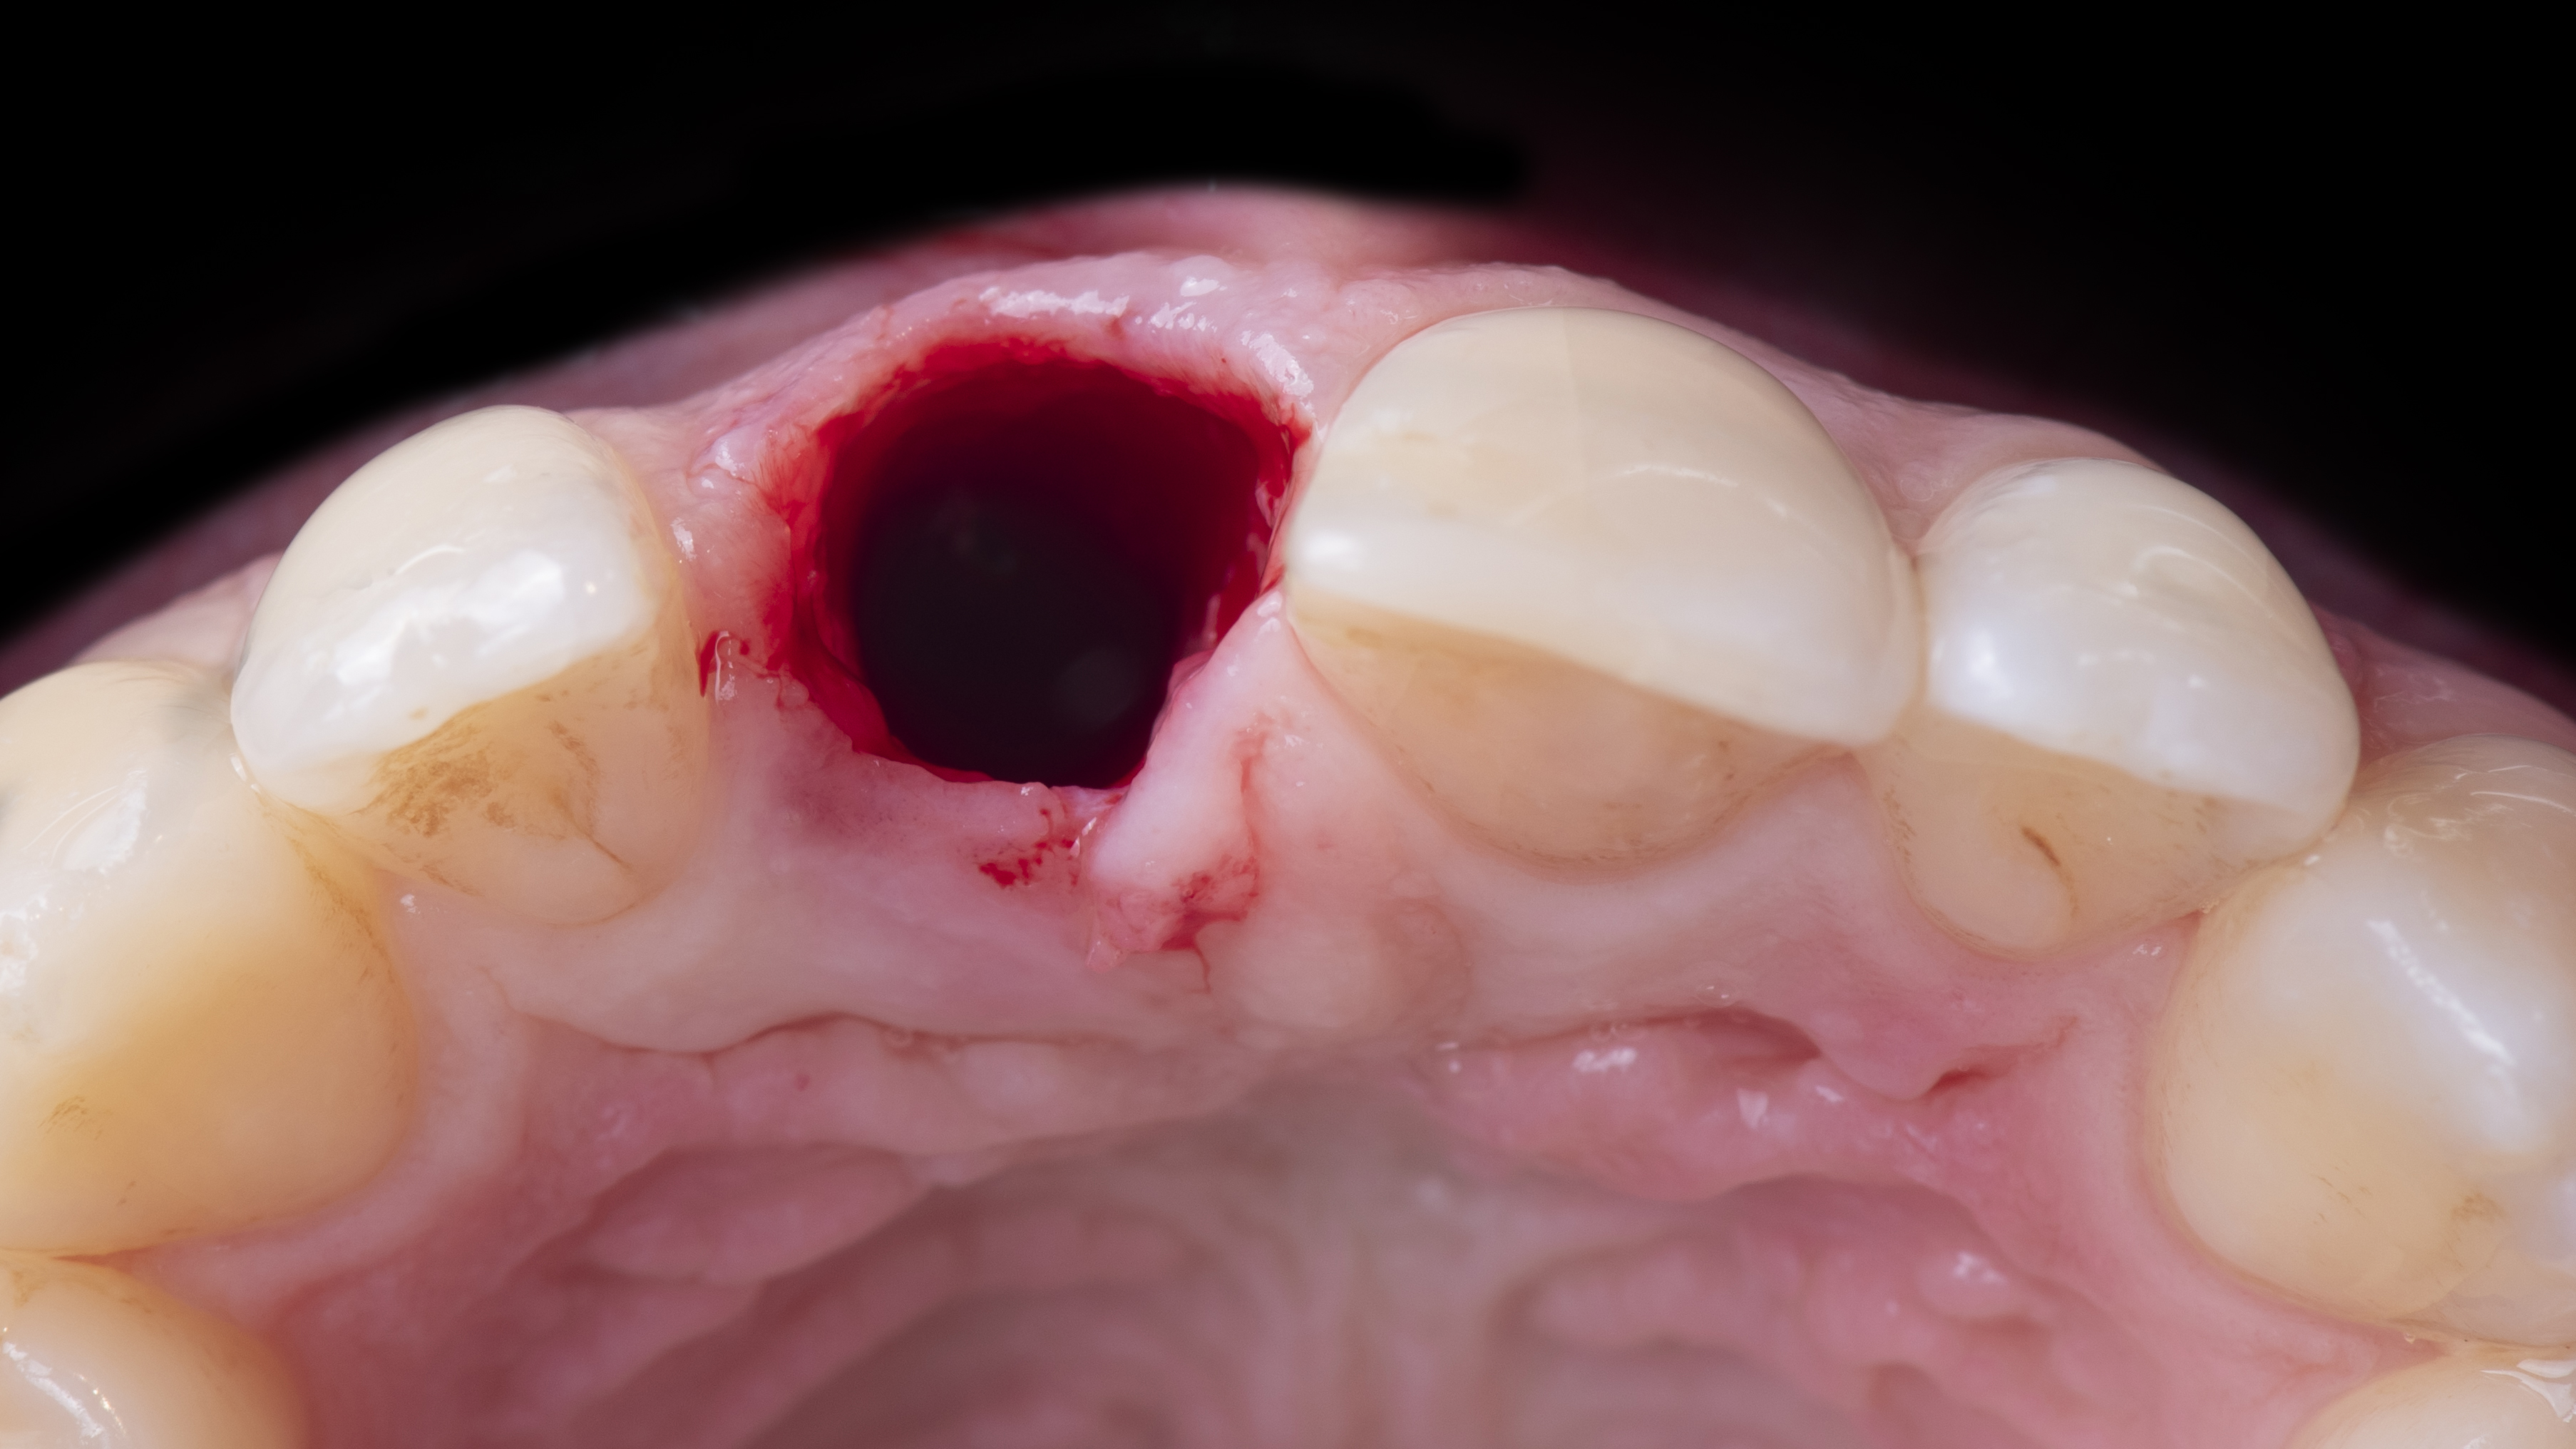

Extraction de la dent la plus atraumatique possible (Photo 10).